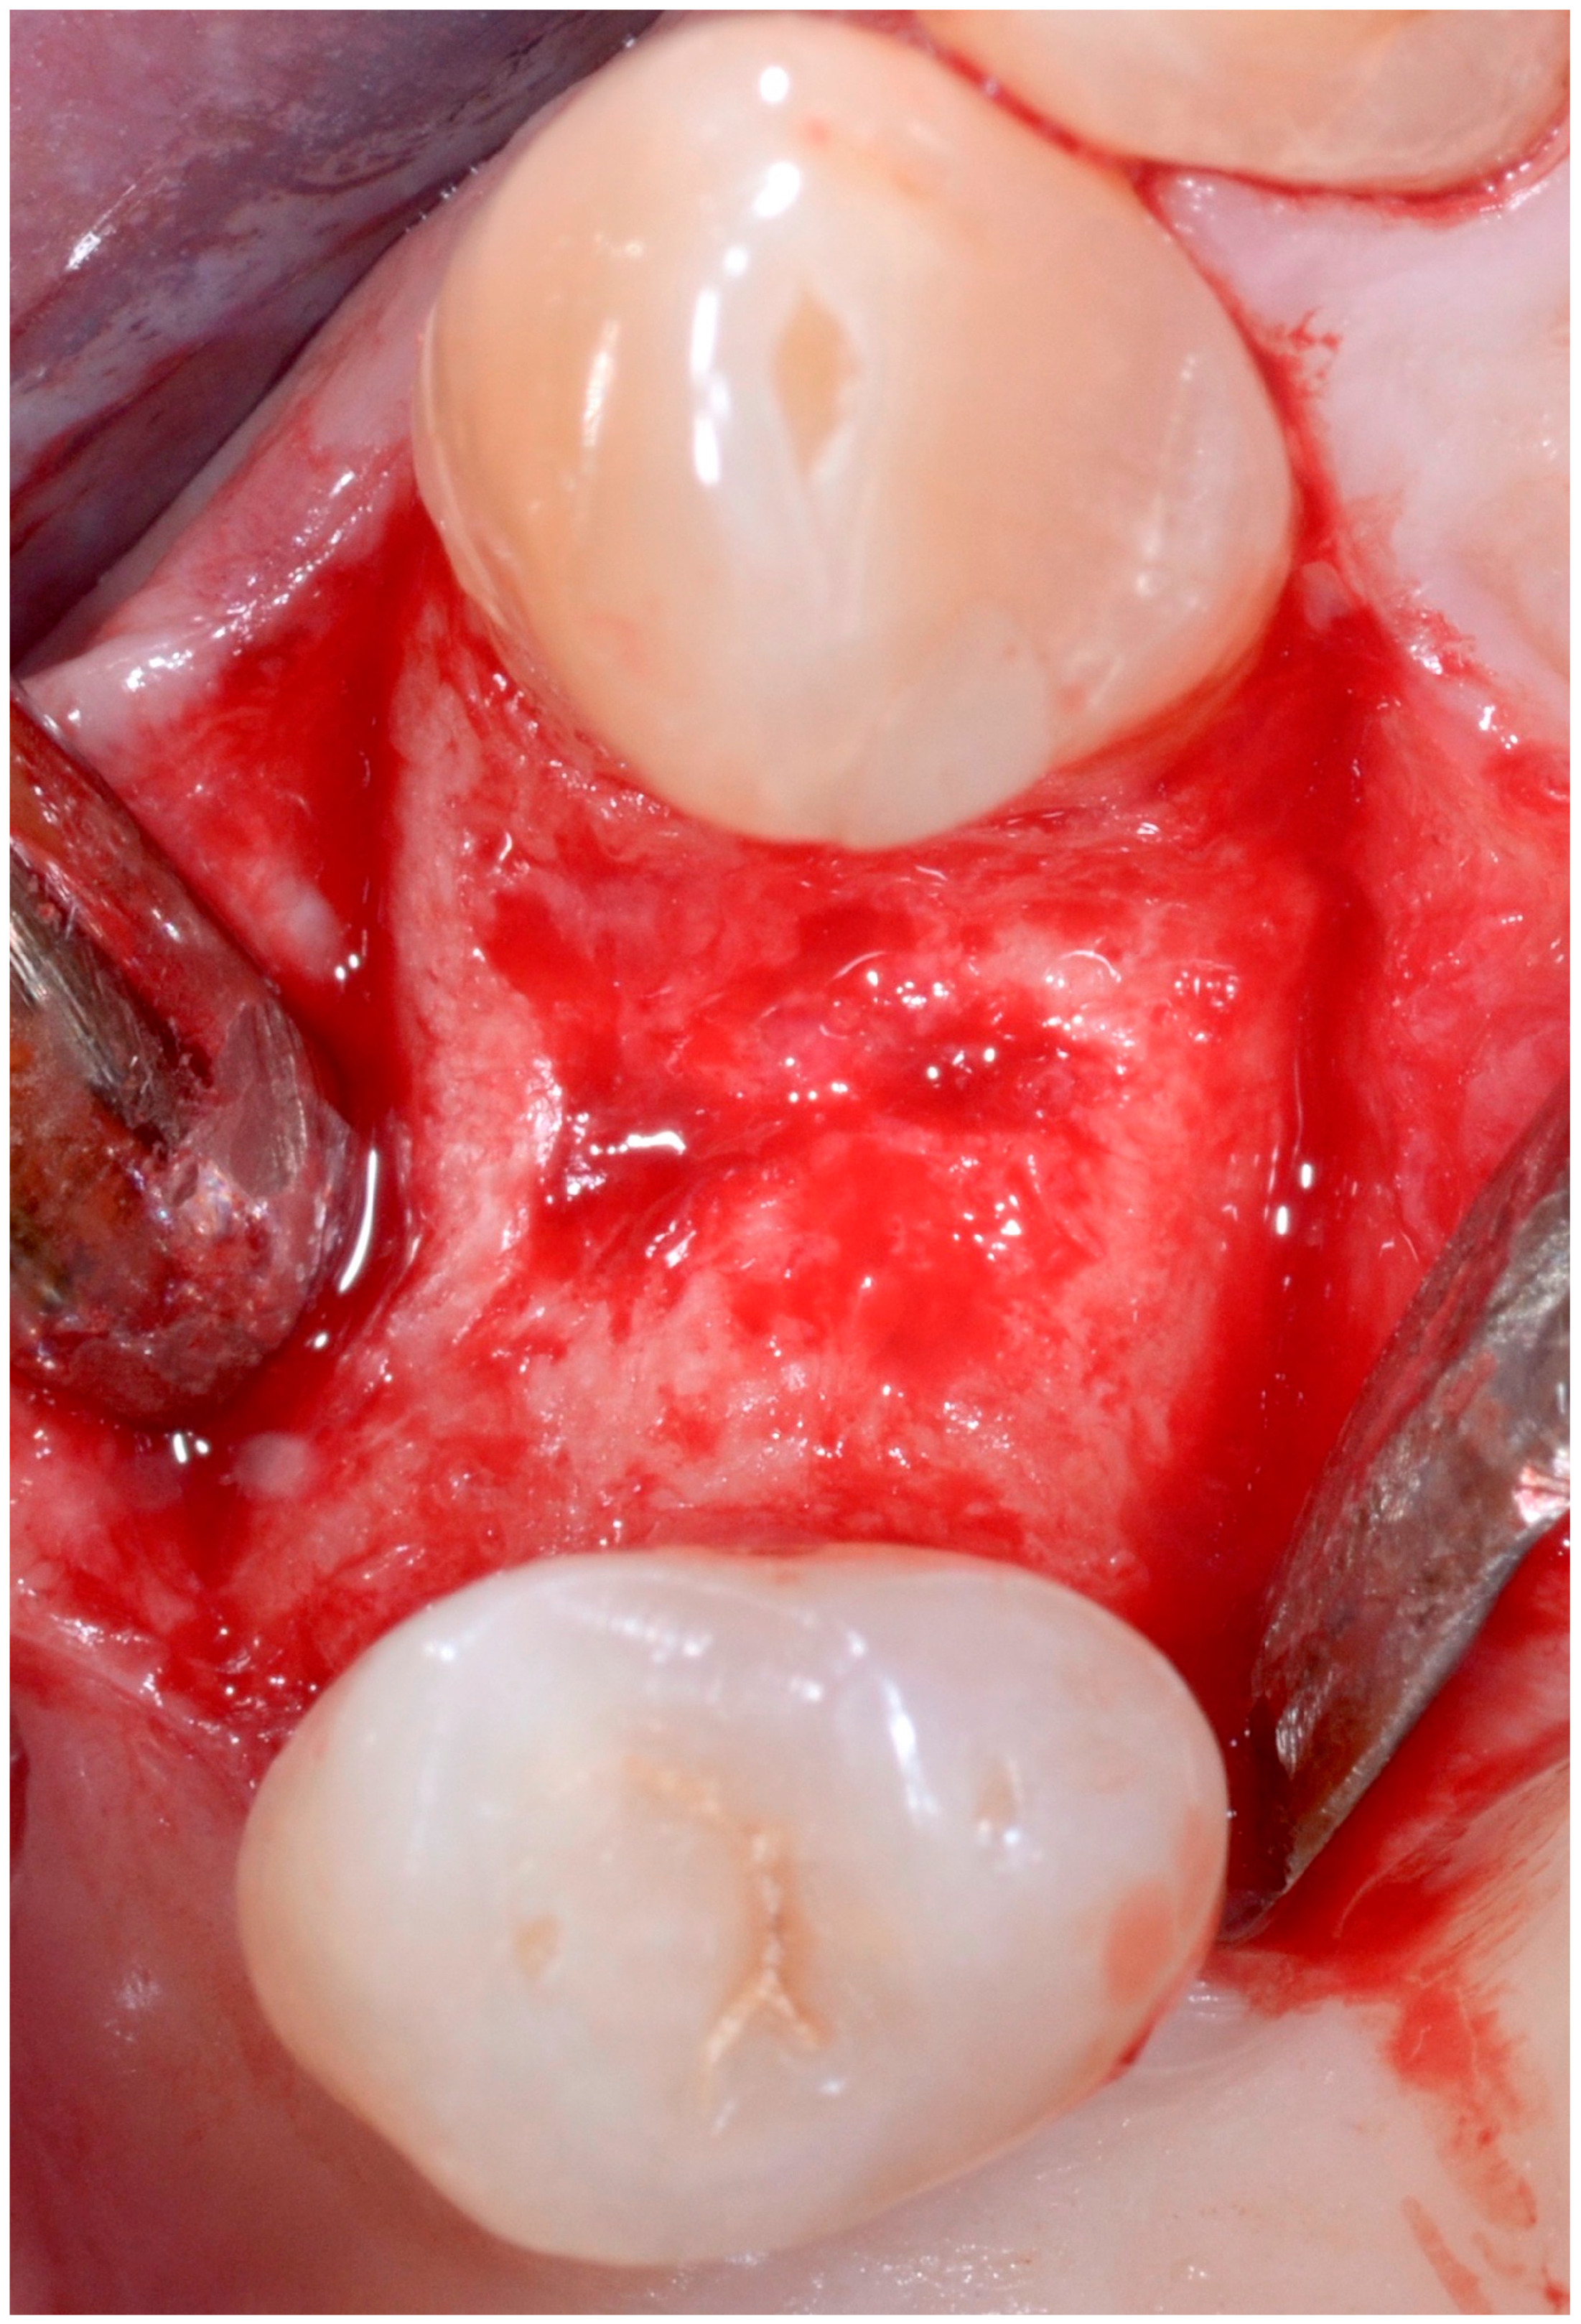

5.4. Surgical Technique

5.5. Implant Placement